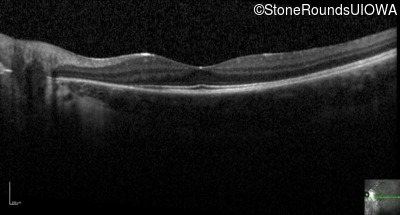

Optical Coherence Tomography - Left - 20/20 -2

Exemplar / OCT Stack